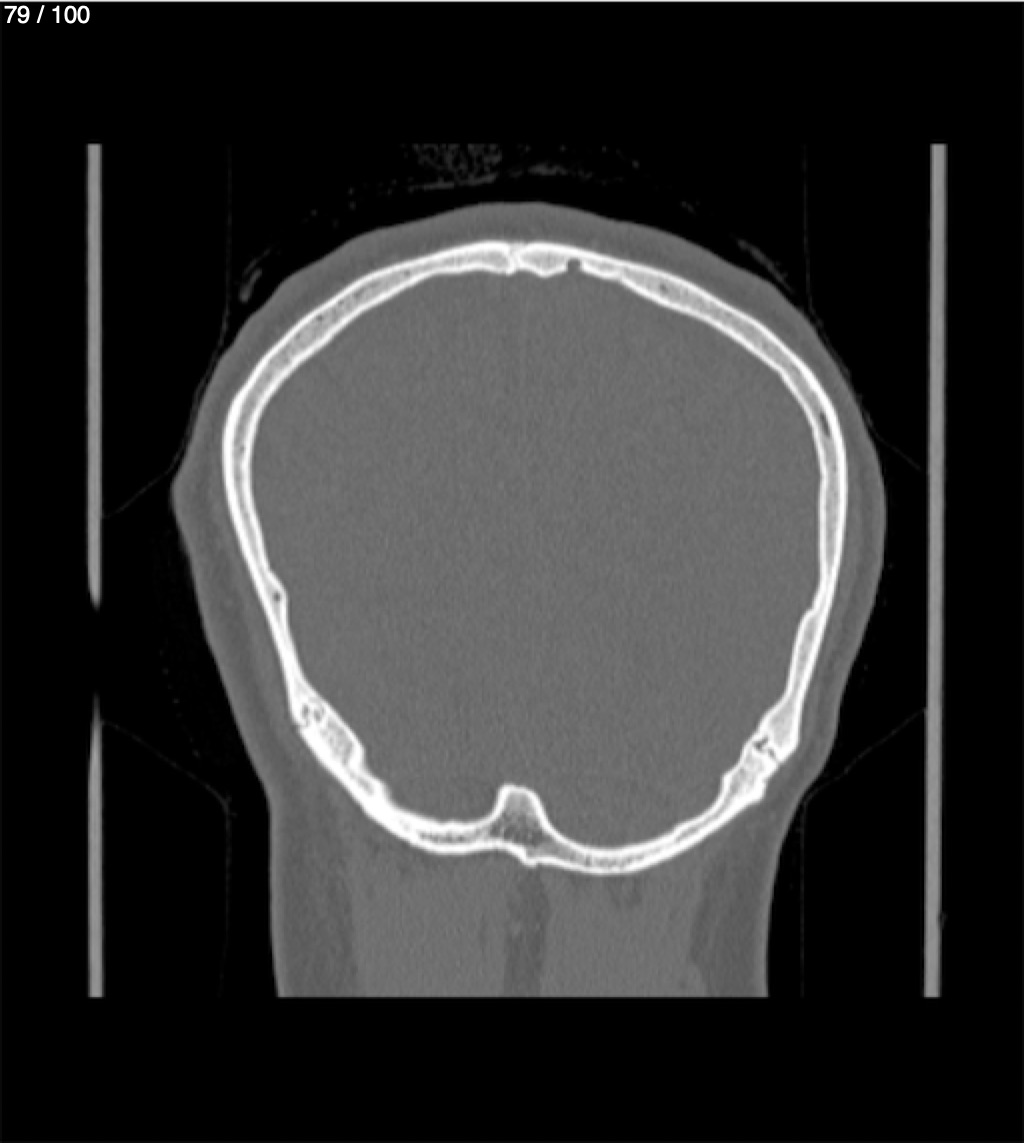

Yonelly Barrios Diaz 35A - T.C Craneo